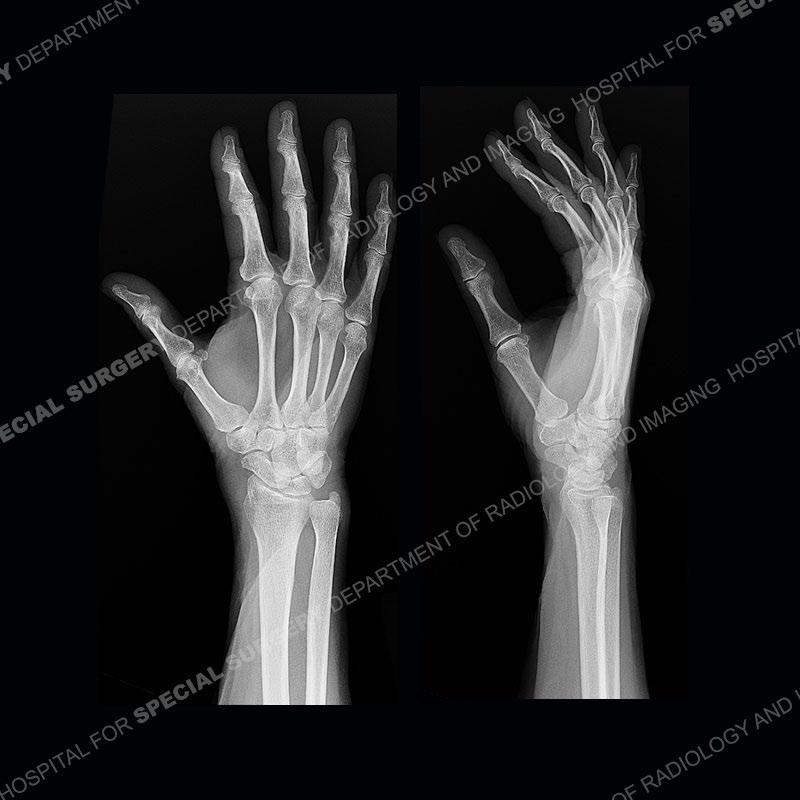

The radiographs in this case are not particularly contributory. The MRI demonstrates tenosynovitis of the first extensor compartment manifest by fluid/synovitis distention of the tendon sheaths. Multiple tendon slips are present of the abductor pollicis longus (APL) and with severe tendinosis seen of one of the tendon slips. Other areas of slightly increased signal and tendinosis are present of the components of the APL. Noted is a somewhat prominent septum separating the more dorsal extensor pollicis brevis (EPB) from the APL.